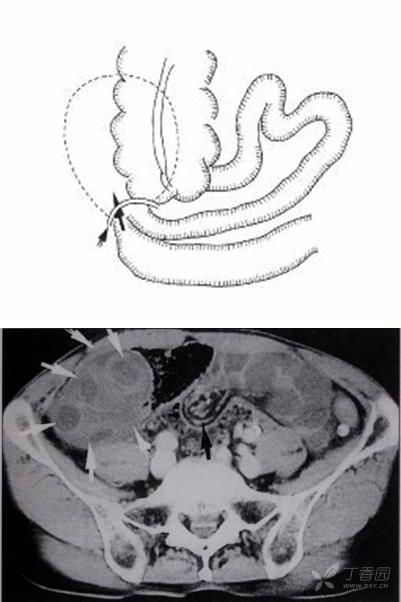

3 經腸系膜裂孔疝:transmesenteric hernia (TMH)

腸系膜是起自Treitz韌帶處,而止于回盲區的扇形腹膜折迭組織,腸系膜裂孔絕大多數為先天發育缺陷。裂孔的缺損大部在2~5 cm之間,疝入腸管多發生在回盲瓣以上50 cm處,故疝入腸管以回腸為主,占87%,易發生腸扭轉。結腸疝入者也見諸于文獻,約占9%。疝入的腸管60%發生絞窄。

臨床上TMH和經大網膜裂孔疝表現近似,發病率約占8%,TMH可分先天發育缺陷和獲得性兩種,70%發病在15歲以內,但平均年齡在50歲以上,說明老年人也是高發病人群,后者可因創傷、手術和炎癥所致。男女之比約為1∶2,視裂孔大小,臨床可出現疝入腸管退出情況,表現為反復發作的慢性過程,但大部份仍為急性腸梗阻甚至發生腸絞窄。

由于從裂孔疝出后并無一限制的疝囊,表現同于一般閉襻型腸梗阻,視裂孔大小,疝入腸管絞窄的嚴重性可能較之一般疝入陷窩者更甚。由于發生裂孔位置不定,又多在其游離緣,故無恒定的腹部CT定位,所以判斷進入疝囊內擁擠、擴張的閉攀腸管及受絞窄增粗、聚集的腸系膜血管非常重要。

急性腹痛,有腹部手術史。 手術診斷: 經腸系膜裂孔疝。